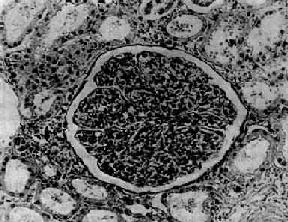

病变为弥漫性,两侧肾同时受累。病变进展较快,主要变化为肾小球内细胞增生。早期,肾小球毛细血管充血,内皮细胞和系膜细胞肿胀增生并有少量中性粒细胞浸润。毛细血管通透性增加,血浆蛋白质可以滤过而进入肾球囊。因此,病人的尿液中常有蛋白、红细胞及白细胞。轻型病人,病变可不再发展,以后逐渐痊愈;比较严重的病例,病变继续发展,肾小球内细胞增生加重。增生的细胞主要为系膜细胞和内皮细胞。增生细胞压迫毛细血管,使毛细血管腔狭窄甚至闭塞,肾小球呈缺血状(图12-7)。此外,肾小球内有多数炎性细胞浸润,主要为中性粒细胞,有时并有少数嗜酸性粒细胞、单核细胞、红细胞、浆液和纤维素性渗出液。镜下,肾小球内细胞数量增多,肾小球体积增大。病变严重时,毛细血管腔内可有血栓形成,毛细血管壁可发生纤维素样坏死。坏死的毛细血管袢破裂出血,大量红细胞进入肾球囊及肾小管腔内,可以引起明显的血尿。不同的病例病变表现形式可能不同。有的以渗出为主,称为急性渗出性肾小球肾炎。有些病变严重,肾小球毛细血管袢坏死,有大量出血者称为出血性肾小球肾炎。

图12-7 弥漫性毛细血管内增生性肾小球肾炎

肾小球内细胞数量增多,系膜细胞和内皮细胞增生并有少量中性白细胞浸润,毛血管腔狭窄